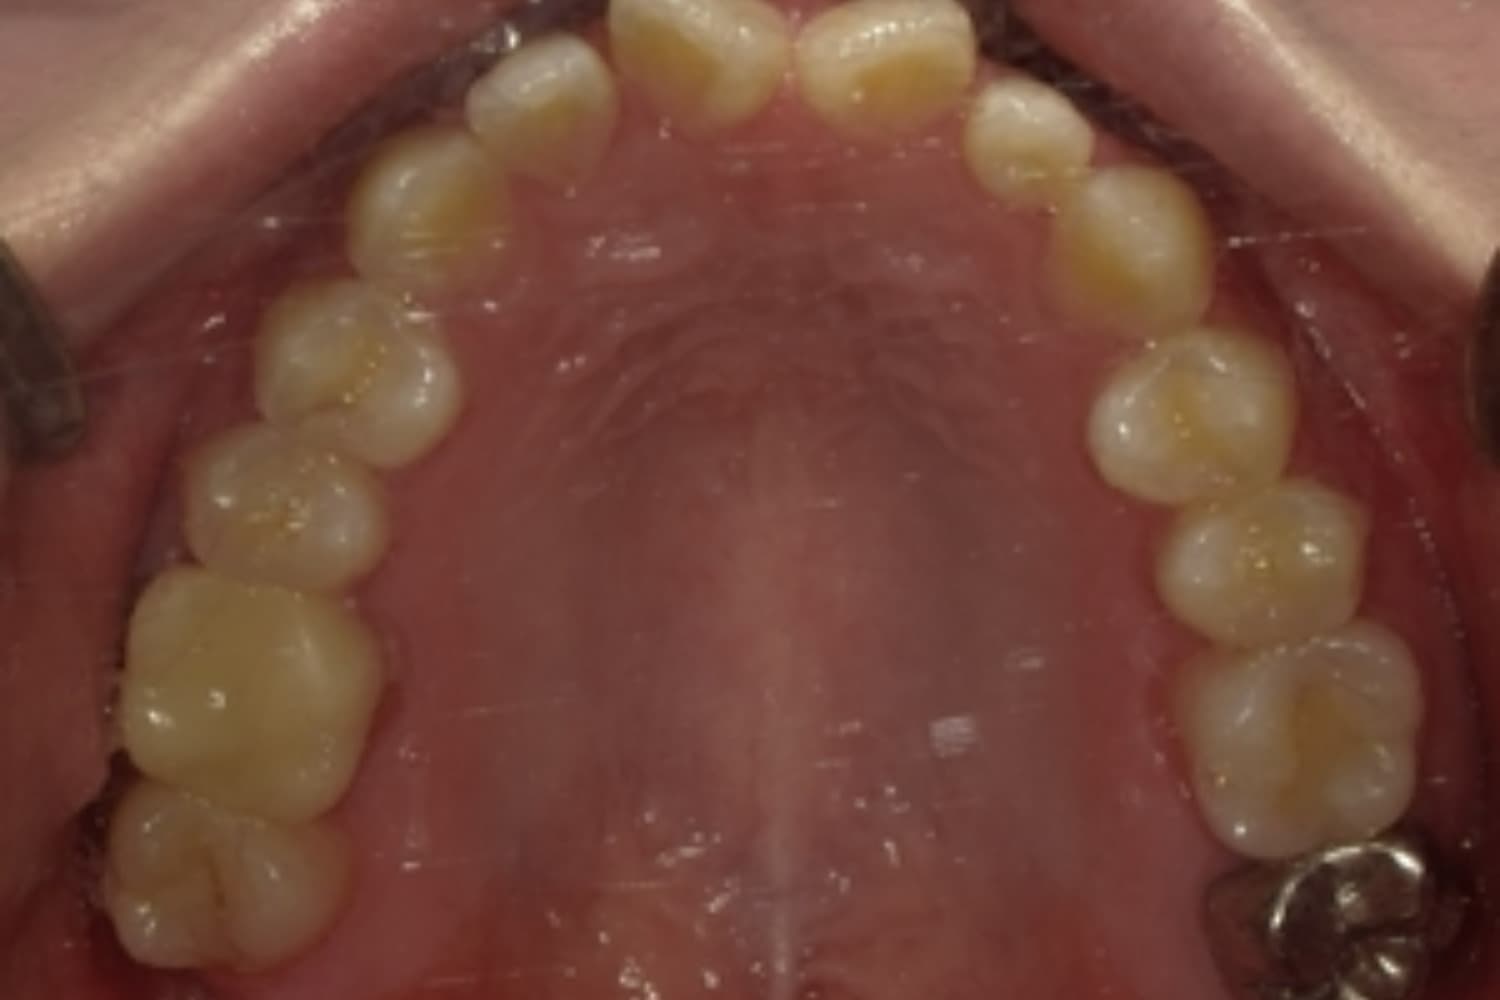

すきっぱ(空隙歯列)2

Before

After

気になる前歯の隙間と前歯のガタガタをマウスピース矯正(インビザライン)にて治療

治療期間

1年

費用

88万円(税込)

副作用・リスク

・矯正治療による歯の動きには個人差があり、想定より治療期間が延びることがあります。 ・矯正治療で歯を動かす際に痛みをともなうことがあります。 ・指示された通りに保定装置を装着しないと、歯並びや噛み合わせの後戻りを引き起こす可能性があります。